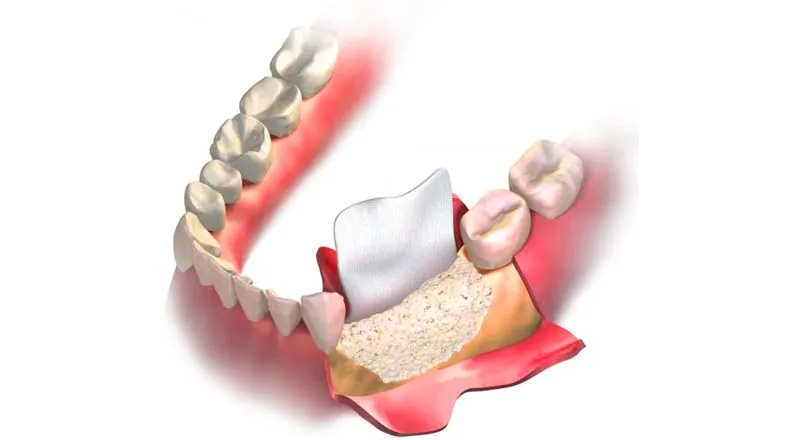

Gömülü Diş Operasyonları: Nedenleri, Süreci ve İyileşme Dönemi

Dental İmplant Cerrahisi: Kayıp Dişlerin Kalıcı ve Güvenilir Çözümü